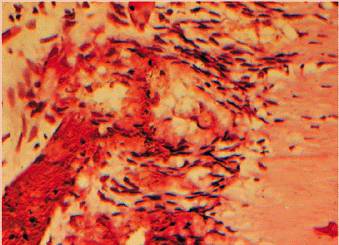

intervention must be considered. Another example of a stressed pulp is the

patient with a maxillary anterior provisional restoration who required local

anesthesia to remove the bridge 12 months after crown preparation and

periodontal therapy because of pain in a maxillary central incisor tooth (Figures 19-38A, and 19-38B). The combined dental procedures

have created stress on the pulpal complex that have exceeded the pulp's ability

to repair. No patient wants to hear why it should have been done after the

Figure 19-38A: Maxillary central incisor with a chronically inflamed (stressed) pulp.

Figure 19-38B: A histologic section of chronic inflammation, irreversible pulpitis, with round cell infiltration. (Photograph courtesy of Dr. Harold R. Stanley.)